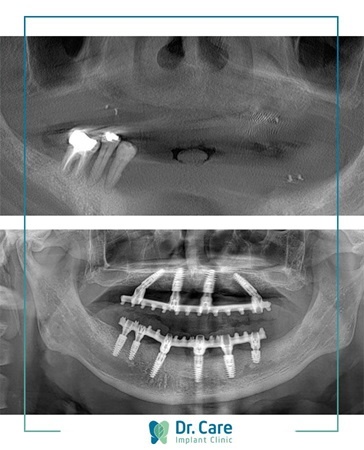

Giải pháp bác sĩ đề ra cho chú là trồng răng Implant All-on-4 toàn hàm trên và All-on-6 toàn hàm dưới. Chia sẻ về chi phí và thời gian trồng răng, chú nói: “Điều tôi thấy may mắn là chọn được nha khoa chuyên sâu về trồng răng Implant. Thời gian lẫn số tiền đầu tư cho răng miệng tôi thấy rất hợp lý”.

| Hình ảnh trước và sau khi trồng răng của chú Jimmy Nguyễn. |